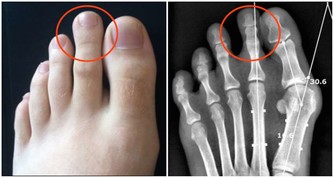

痔瘡症狀嚴重,通過改善以上家庭療法還無法消除症狀時,也可以考慮膠圈套紮法,即在痔瘡根部套入小型膠圈,痔瘡逐漸缺血、壞死。紅外線光凝、冷凍等,都是通過冷熱刺激,直接使痔瘡壞死。

當症狀嚴重,出現痔核嵌頓等嚴重影響到正常生活的症狀時,就要考慮對痔瘡進行手術切除了。